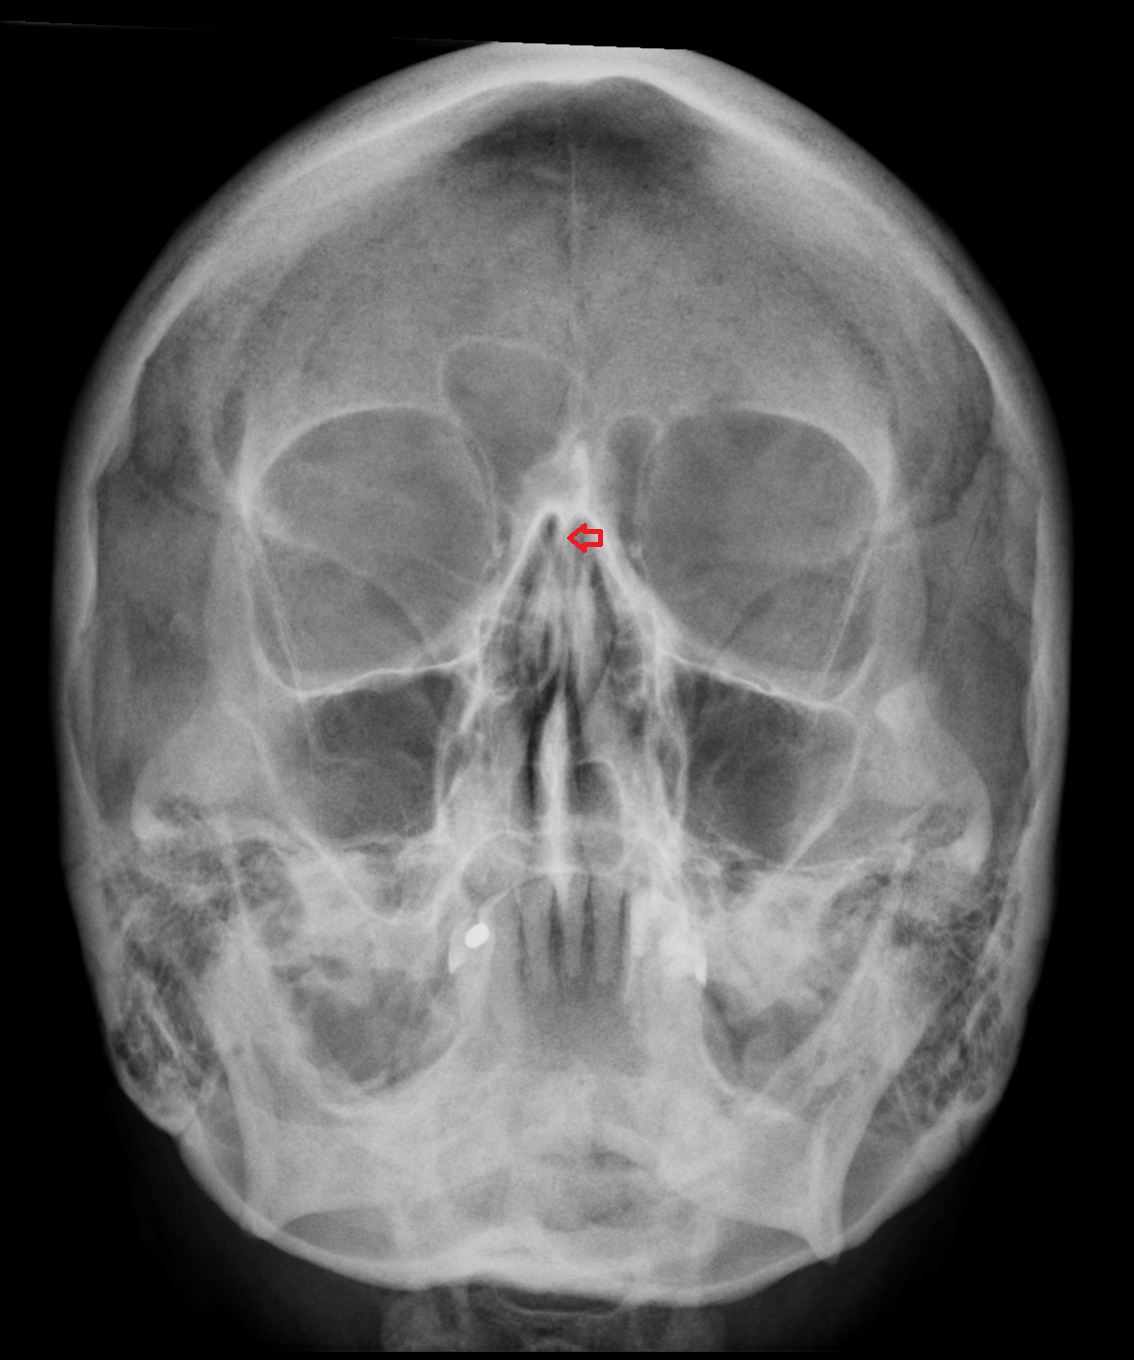

- Nasolacrimal duct (Tear duct)